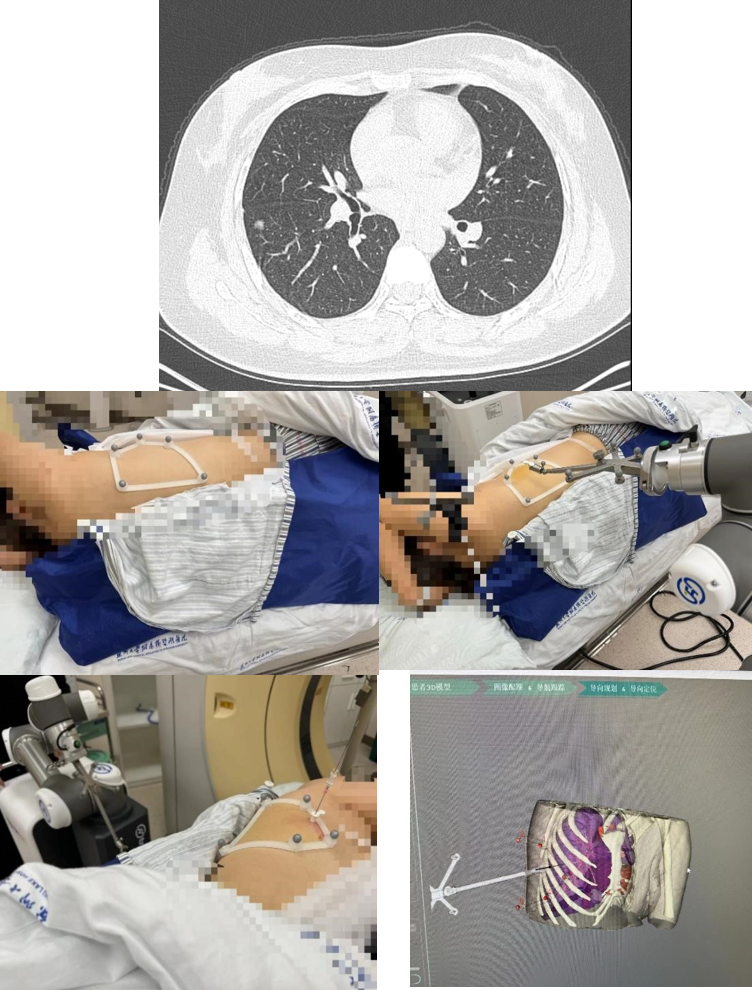

患者右下肺大小8mm的混合磨玻璃结节位于背段气管以上肺组织外三分之一处;另右中肺大小6mm的磨玻璃结节位于水平裂边缘,且患者水平裂发育良好,可直接行右中肺结节楔形切除术。结合患者本人意愿,马海涛教授为其制定右中肺结节楔形切除术及右下肺结节定位后节段切除术的手术方案,精准定位及精准切除的同时,尽最大可能减少患者的肺功能损失。马海涛教授带领其团队充分讨论该患者的定位方案,决定使用“机器人穿刺导航定位系统”为该患者进行术前定位。该技术人机结合,通过病灶提取、路径规划、光学导航、穿刺实施等步骤完成术前定位工作,减少术中肺组织切除范围。相较于传统定位技术,该机器人定位系统在定位安全性、定位准确性、定位稳定性、定位效率上均有所提高,优势显著。

定位过程中,机器人快速的三位重建及路径规划步骤